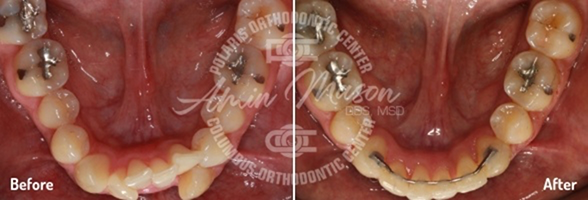

Case 4

This 26-year-old patient wanted to straighten her severely crooked teeth because they made her feel self-conscious. Not wanting to draw any more attention to her teeth, she decided to get Invisalign. Multiple orthodontists told her that her case was too complicated for Invisalign treatment, but she persisted and eventually found Dr. Mason. He was able to combine Invisalign with a class II corrector and elastics to fully address all her issues. After going through the process, she said she was extremely happy with the results and could not stop smiling.